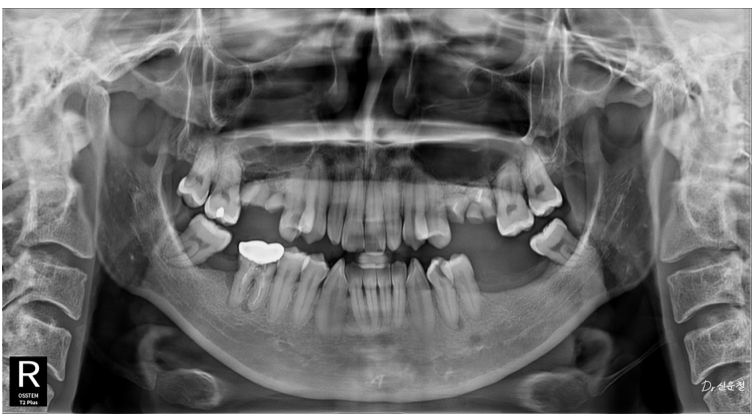

촬영일 250327

하지만 정밀 검진 결과, 깊게 진행된 사랑니 충치 뿌리만 남은 치아

잇몸뼈가 녹아 흔들리는 어금니 가 확인되었습니다.

통증이 없었던 것뿐,

문제는 이미 상당히 진행된 상태였습니다.